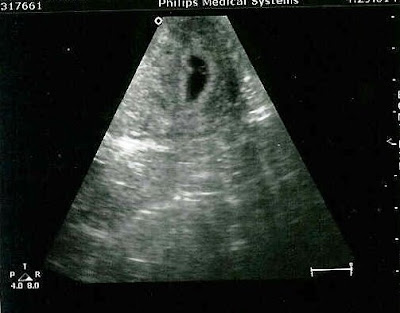

Rachel's baby at 5 weeks, 6 days -- Fetal sonogram images from pregnancy

We were able to have a sonogram done at 5 weeks.

The sonogram shows, that as of Nov. 25th, the baby is 5 weeks 4 days old.